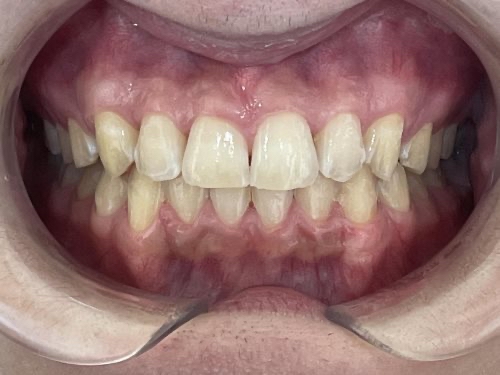

噛み合わせの位置が改善され、歯並びもきれいになりました。

患者様には「すごくきれいになった」と大変ご満足いただきました。